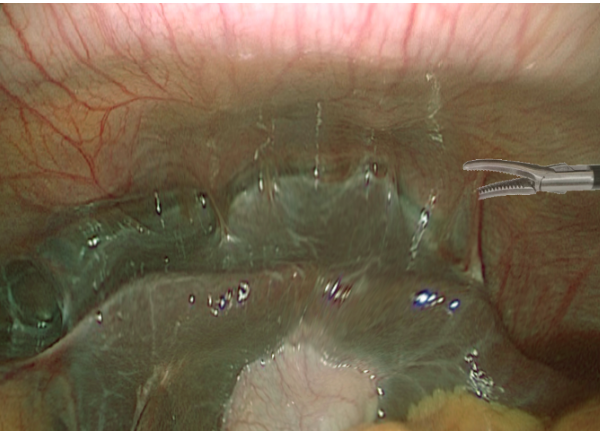

What is this pathology depicted? [1]

Which pathogens are most likely to have caused this? [1]

Fitz-Hugh syndrome

C. trachomatis and N. gonorrhea

A diagnostic laparoscopy was performed that showed extensive adhesions between the liver and abdominal wall (anterior wall). What is the next step in the management of the patient?

A. Ceftriaxone plus doxycycline

B. Lyse the adhesion with electrocautery

C. Metronidazole and doxycycline

D. No management is required